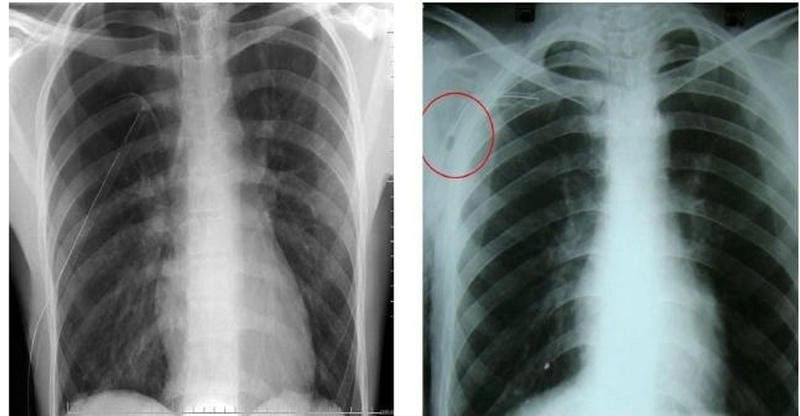

Bạn sẽ phải rùng mình khi chiêm ngưỡng hình ảnh bệnh lao phổi là như thế nào dưới ống kính y học thực tế. Những bức ảnh chụp X-quang cho thấy phổi bị tổn thương nặng, xuất hiện những đốm trắng mờ như bóng ma ám ảnh. Không chỉ là các tổn thương vật lý, đây còn là những “chứng tích sống” của căn bệnh âm thầm hủy hoại cơ thể qua từng hơi thở. Từ viêm nhẹ đến tổn thương lan rộng, hình ảnh bệnh lao phổi khiến người xem không thể rời mắt vì mức độ nghiêm trọng mà nó thể hiện rõ ràng qua từng chi tiết.

So sánh lao hình ảnh phổi bình thường dễ nhận biết